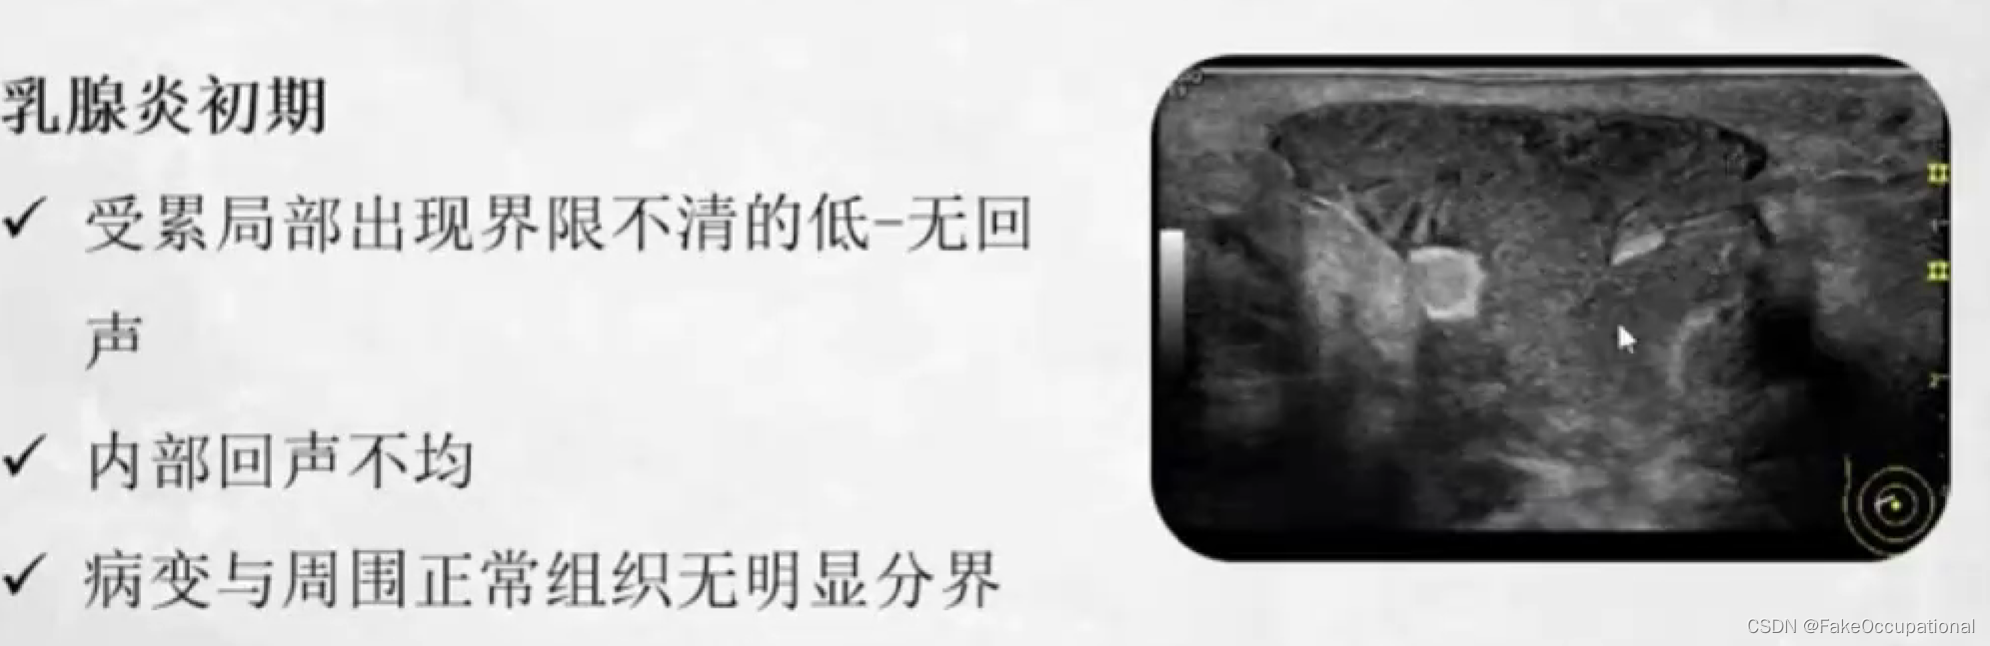

乳腺炎

- 临床表现有不同程度发热患处乳腺红肿、疼痛、乳腺肿块患侧腋下淋巴结肿大